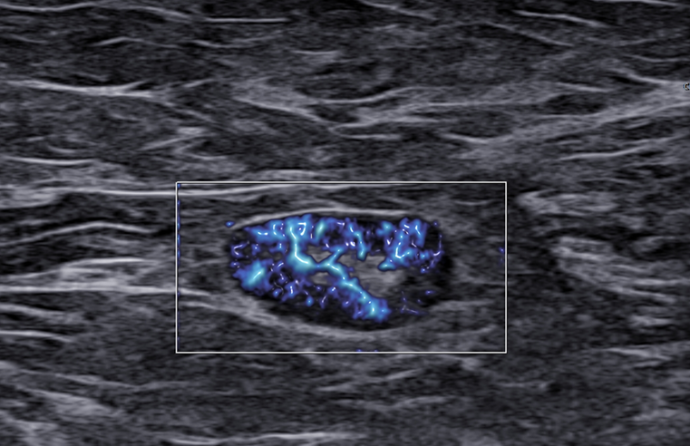

Czy podział BIRADS 4 ma sens?

Jak radzić sobie z BIRADS 4a, b, c? – morfologiczne wskazówki

Ultrasonografia jest jedną z czterech głównych metod w diagnostyce chorób piersi. Współczesna sytuacja epidemiologiczna, czyli ciągły wzrost zachorowań na raka piersi u kobiet, wymaga od nas dyskusji na ten temat.